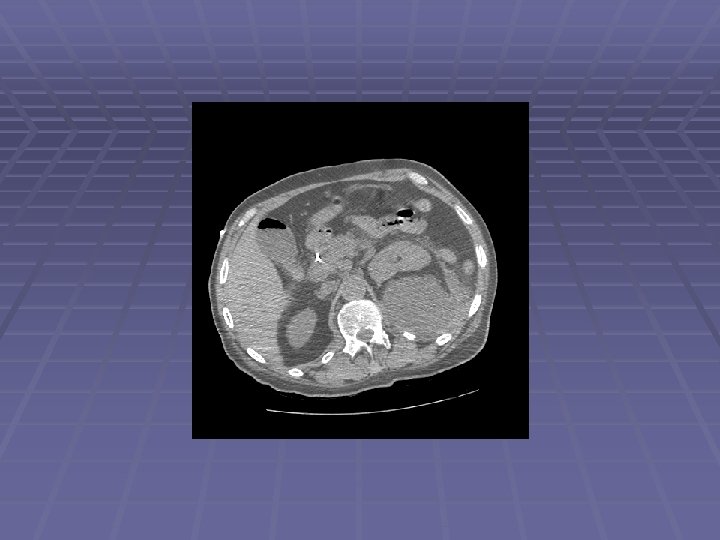

Patient DD 62 y. o. man with history of alcoholism and recurrent pancreatitis since the 1970’s, admitted to an outside hospital with jaundice MRI showed a large pancreatic head mass ERCP for biliary drainage – failed Complicated PTC by pancreatic tail pseudocyst formation with internalization - successful Patient left AMA and came to JMC EUS/FNA performed to obtain diagnosis

Endosonographic Evaluation EUS Large ~30 mm hypoechoic pancreatic head mass surrounding the intrapancreatic CBD with PTC drain seen within CBD Dilated PD to 5 mm with evidence of chronic pancreatitis FNA performed